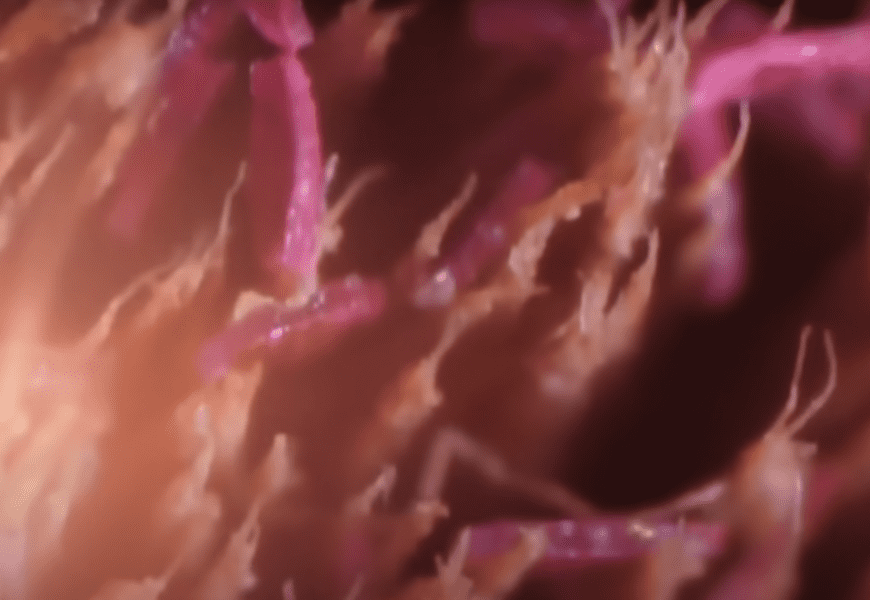

11. Kidney

This image is a light micrograph of a contracted kidney displayed under a microscope. It doesn’t really resemble anything, certainly not a kidney.